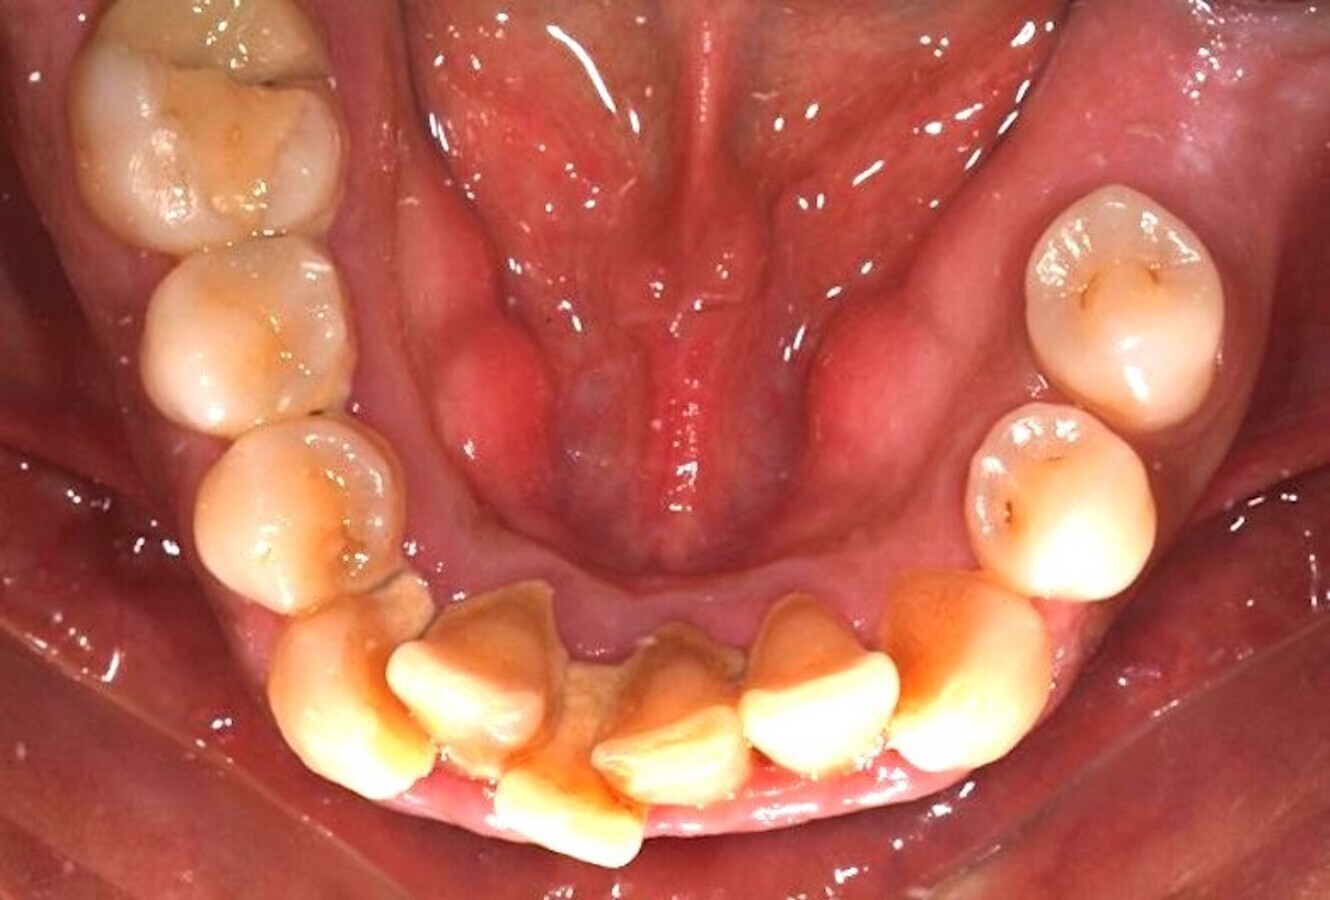

En la cirugía de tejidos blandos, la gingivectomía es probablemente uno de los tratamientos más básicos y que más frecuentemente se realizan en periodoncia quirúrgica (Figuras 17-19). Realizar una gingivectomía con láser es un procedimiento muy sencillo y a la vez bastante rápido que produce un efecto inmediato y que, comparado con una gingivectomía convencional con bisturí, ofrece una serie de ventajas como por ejemplo una hemostasia excelente, lo que mejora la visibilidad del campo y resulta en una molestia postoperatoria mínima para el paciente11.

La gingivectomía con láser es un procedimiento muy rápido y sencillo que ofrece beneficios comparado con una gingivectomía convencional (ver Figuras 17-19).

Fig. 17.

Fig. 18.

Fig. 19. Las figuras 17-19 muestran que la gingivectomía con láser es un procedimiento muy rápido y sencillo que produce un efecto inmediato y ofrece ventajas comparado con la gingivectomía convencional con bisturí.

Cuando el aumento del volumen de los tejidos blandos es grande y generalizado, estos agrandamientos gingivales son medicamentosos, y es en estos casos en los que la utilización del láser presenta ventajas realmente importantes y llamativas frente a la técnica convencional (Figuras 20 y 21).

Figuras 20 y 21. Las figuras 20 y 21 indican que en los agrandamientos gingivales voluminosos, la utilización del láser presenta ventajas llamativas frente a la técnica convencional.

Mavrogiannis y colaboradores publicaron un trabajo en el que compararon tres técnicas quirúrgicas diferentes para este tratamiento y concluyeron que la cirugía de colgajo no ofreció ventajas frente a la gingivectomía convencional respecto a recurrencia y que el índice de recurrencia fue significativamente menor en pacientes tratados con láser12.